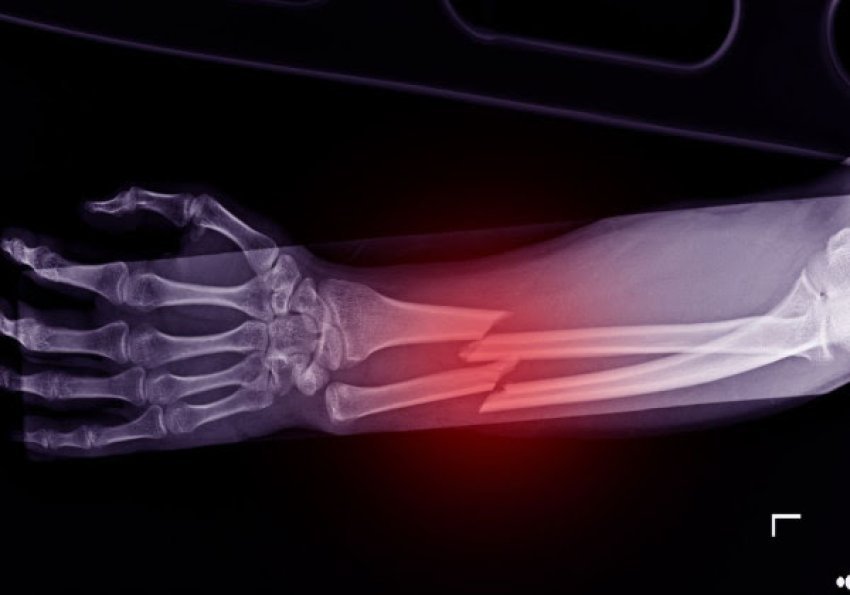

Shkencëtarët kinezë kanë zhvilluar një ngjitës kockash të ri të quajtur ”Bone-02”, që është i aftë të riparojë frakturat në vetëm tri minuta me një injeksion të vetëm, i frymëzuar nga mënyra se si ngjiten ostriket në kushte lagështie, shkruan italianstonic.it.

Ai siguron një lidhje shumë të fortë dhe tretet ndërsa kocka shërohet duke shmangur kështu përdorimin e pllakave metalike ose vidave.